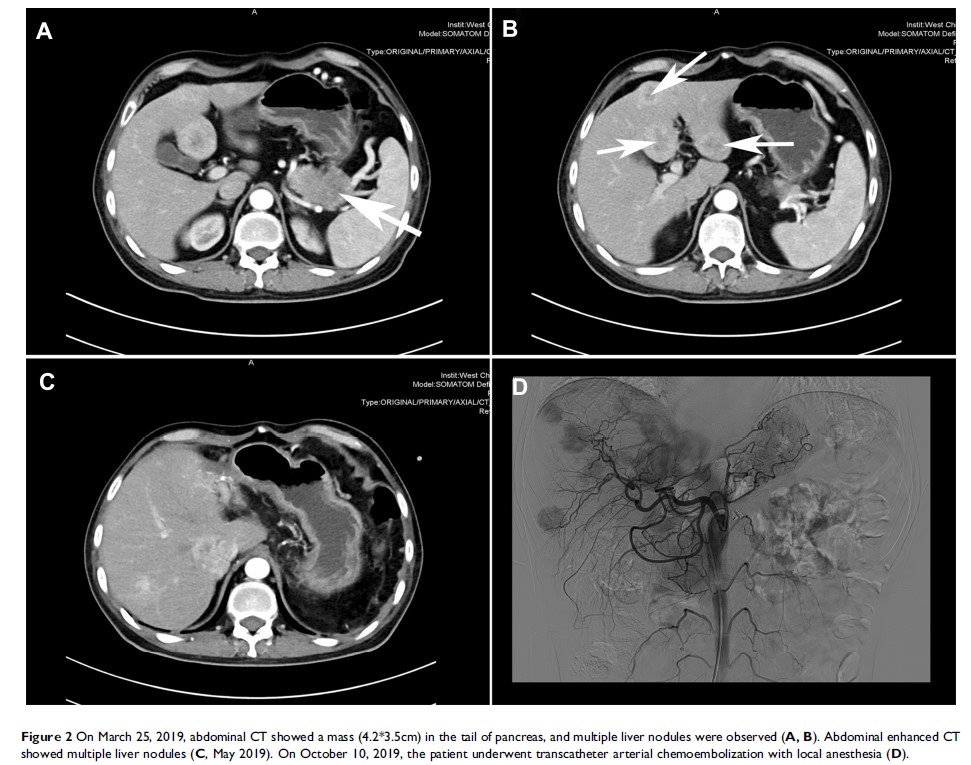

应用生长抑素、化疗联合 TAE 治疗伴有坏死松解性游走性红斑的异质性胰高血糖素瘤